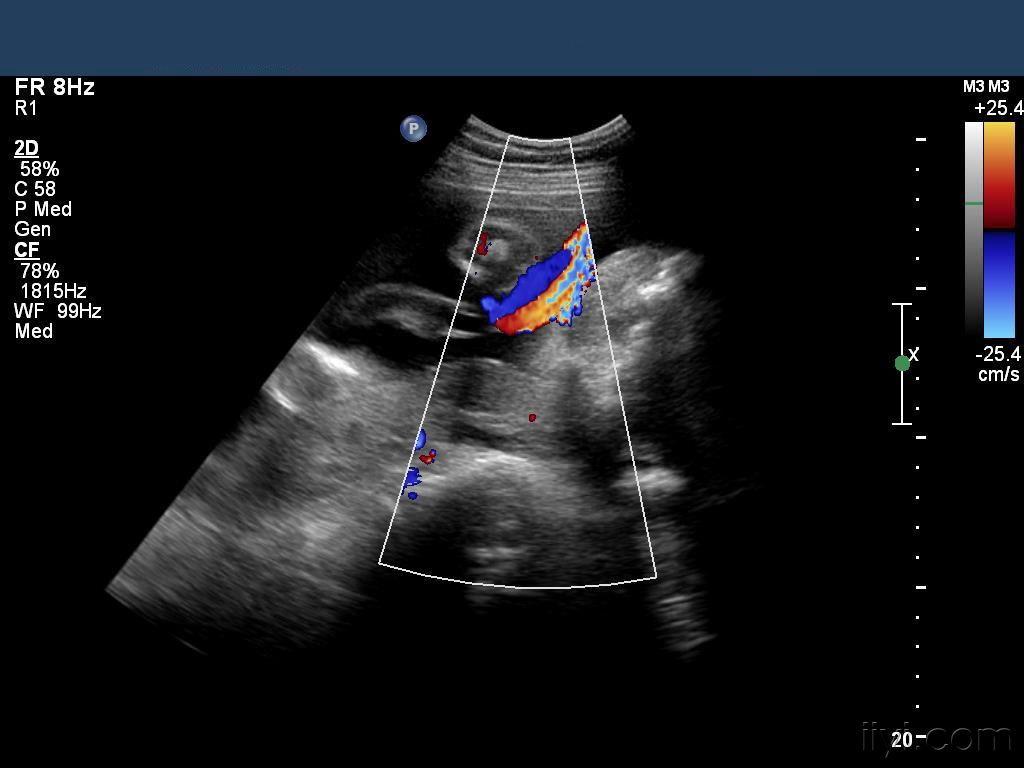

b超检查出胎儿单脐动脉,要不要紧?

单脐动脉